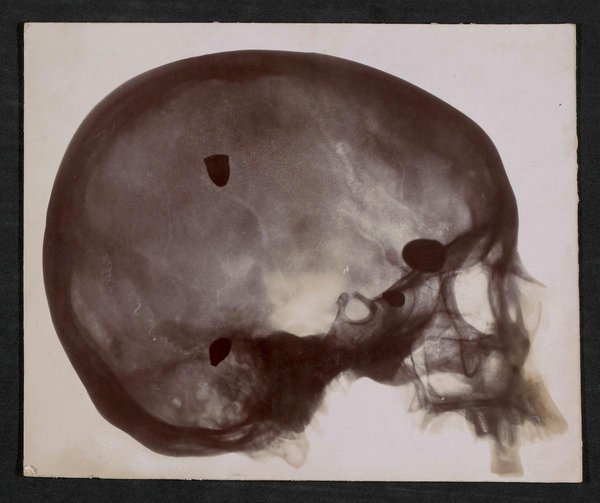

Die Fotografie wurde vermutlich vom Physikalischen Dienst der Fakultät für Medizin und Pharmazie, Toulouse, erstellt. Rückseitig mit handschriftlichen Anmerkungen: Epreuve gouche (=Probe links); bord interne (=innerer Rand); Einl. No. 69 von 24/VII. 1900 Widm. von Dr. C. Marie, Toulouse, Bl. 5; 13070.